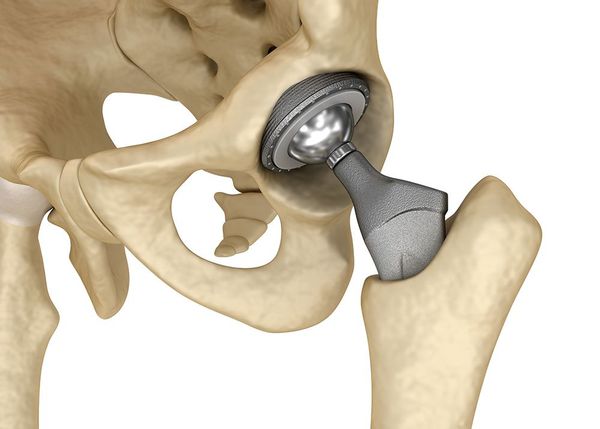

Эндопротезирование тазобедренного сустава: фото и схемы